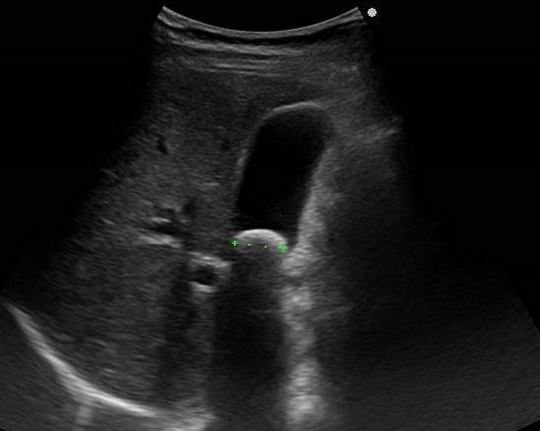

腹部超音波検査やCT検査、血液検査、核磁気共鳴胆管膵管撮影や内視鏡を用いた胆管膵管造影検査で診断されます。加齢とともに増加し、中高年以上に好発します。

血液検査、腹部超音波検査やCT検査で診断されます。